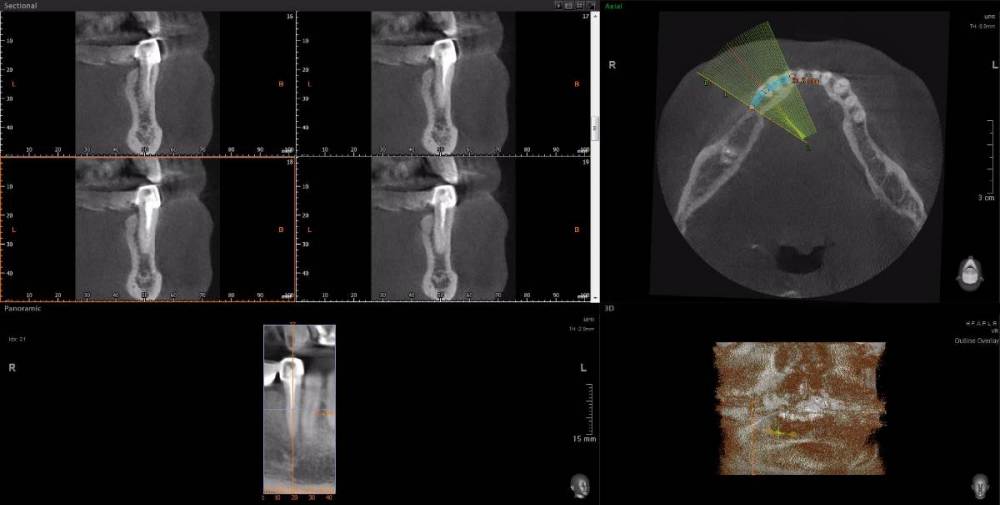

Dude Опубликовано 1 апреля, 2021 Поделиться Опубликовано 1 апреля, 2021 По плану в 1 этапе, кроме остального: лечение каналов и укрепление их стекловолоконными штифтами: 16, 25, 27, 44, 47; имплантация 14, 15, 17, 12, 11, 21, 22, 24, 26, 36, 37, 46, 45. Во 2 этапе (через 5-6 месяцев) установка коронок. Лечение в другой стране. Чтобы сократить длительность первого этапа, предложили лечение зубов сделать на 2 этапе. Очень засомневался, можно делать имплантацию с невылеченными зубами? Ссылка на комментарий

Dude Опубликовано 1 апреля, 2021 Автор Поделиться Опубликовано 1 апреля, 2021 https://disk.yandex.ru/d/6d0pmZ1zArn1Og Так? Ссылка на комментарий